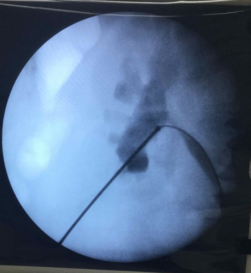

Puncture of the kidney using Chiba needle and guide wire passed down

The procedure is done under general anesthesia.  A small tube called a ureteral catheter is placed through the urinary bladder by using a telescope called a cystoscope.  Then the patient is placed on prone position for the main procedure.  The kidney is identified through fluoroscopy or C-arm guidance by injecting radiographic dye into the earlier placed ureteral catheter.  Once the kidney and puncture site are identified, a small incision is made.  The kidney access starts with puncture of a Chiba needle into the identified site under fluoroscopic guidance.  Backflow of urine into the needle means that access was successful.  A guidewire is then passed into the needle and serial dilation of the tract is made until a special instrument called an Amplatz sheath can be accommodated.  This sheath will be the working port where the operating telescope called a nephroscope is inserted.  The stone will be broken into small fragments with the use of a device called a lithotriptor.  Then the fragments are evacuated.  The kidney is checked by fluoroscopy for any residual fragments.  Then a tube called a double J stent is inserted through the nephroscope down to the bladder to ensure drainage and prevent blockage of small stone fragments that might have fallen into the ureter.  Another tube called a nephrostomy tube is placed on the puncture site after removal of the Amplatz sheath.